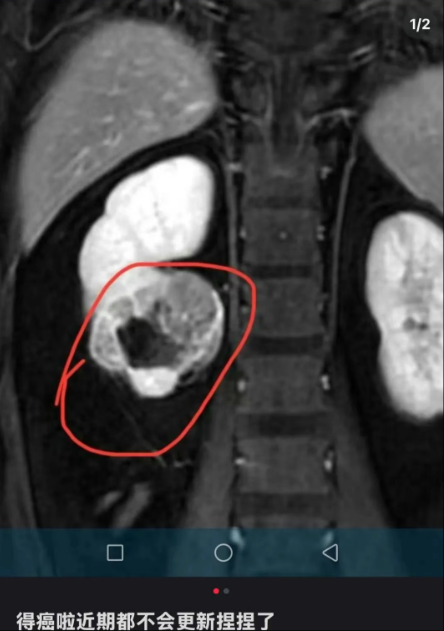

该博主在社交媒体上发文透露自己罹患肾癌,并宣布将暂时停止更新与“捏捏”玩具相关的视频内容。该博主最新更新透露病情:肾脏有部分坏死,即将进行手术。

该博主在社交平台宣布罹患癌症。图源其账号截图